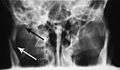

Nondisplaced fracture of the mandible

Plain film radiography

Traditionally, plain films of the mandible would be exposed but had lower sensitivity and specificity owing to overlap of structures. Views included AP (for parasymphsis), lateral oblique (body, ramus, angle, coronoid process) and Towne's (condyle) views. Condylar fractures can be especially difficult to identify, depending on the direction of condylar displacement or dislocation so multiple views of it are usually examined with two views at perpendicular angles.[10]